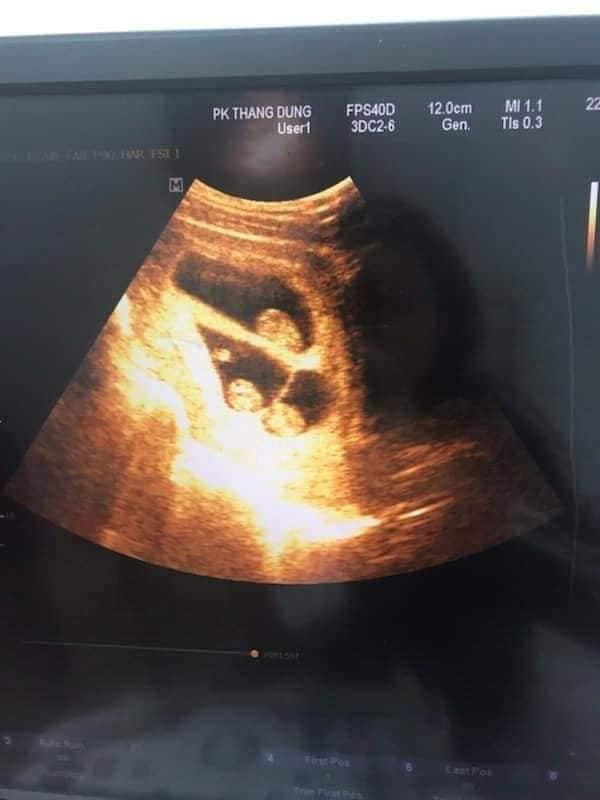

Mới đây, trên mạng xã hội lan truyền bài viết của một ông bố với tựa đề "vợ sinh ba là cảm giác như thế nào" khiến nhiều người quan tâm. Anh chồng chia sẻ khi siêu âm nghe 3 tim thai, anh "sướng rơn người".

"Tôi thề là thích lắm các bác ạ, lúc đi siêu âm nghe bác sĩ báo có 3 thiên thần thôi mà sướng rơn người. Trước mình cứ nghĩ muốn sinh ba phải can thiệp kiểu chuyển phôi thì mới có ai dè mình lớ ngớ vớ huy chương luôn. Vừa viết mà vừa cười miệng rộng ngoác ra đây." - Anh Đông vui vẻ chia sẻ lại cảm giấc lâng lâng khi làm bố.